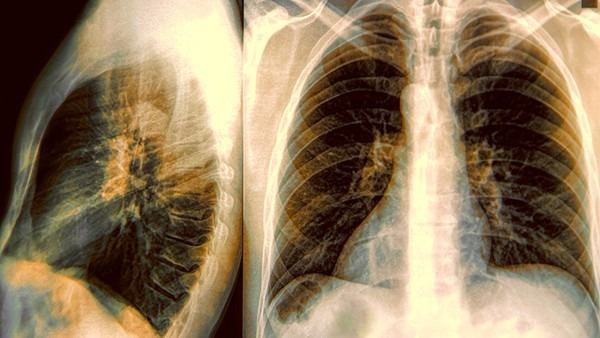

支气管结核狭窄在患者初次患病时会出现,在治疗和康复过程中症状逐渐减轻。然而,如果病情得不到很好的控制和治疗的话,支气管结核狭窄可能会进一步加重,甚至可能出现并发症。

支气管结核狭窄继续加重的原因主要有以下几点:首先,原发病灶没有得到根本的治愈,结核病灶会继续扩散和恶化,导致狭窄情况进一步加重。其次,患者自身的自疗方式不当,比如没有按时用药、用药不规范等,也会影响治疗效果,使狭窄情况无法得到很好的控制。再者,如果患者有其他合并症,如肺气肿、合并结核等,这些疾病本身也会导致支气管狭窄的加重。

可以说,支气管结核狭窄是否会继续加重,主要取决于病情的控制和治疗的效果。对于已经形成的狭窄病变,恢复到正常状态比较困难,但是可以通过积极的治疗来控制疾病的进展。